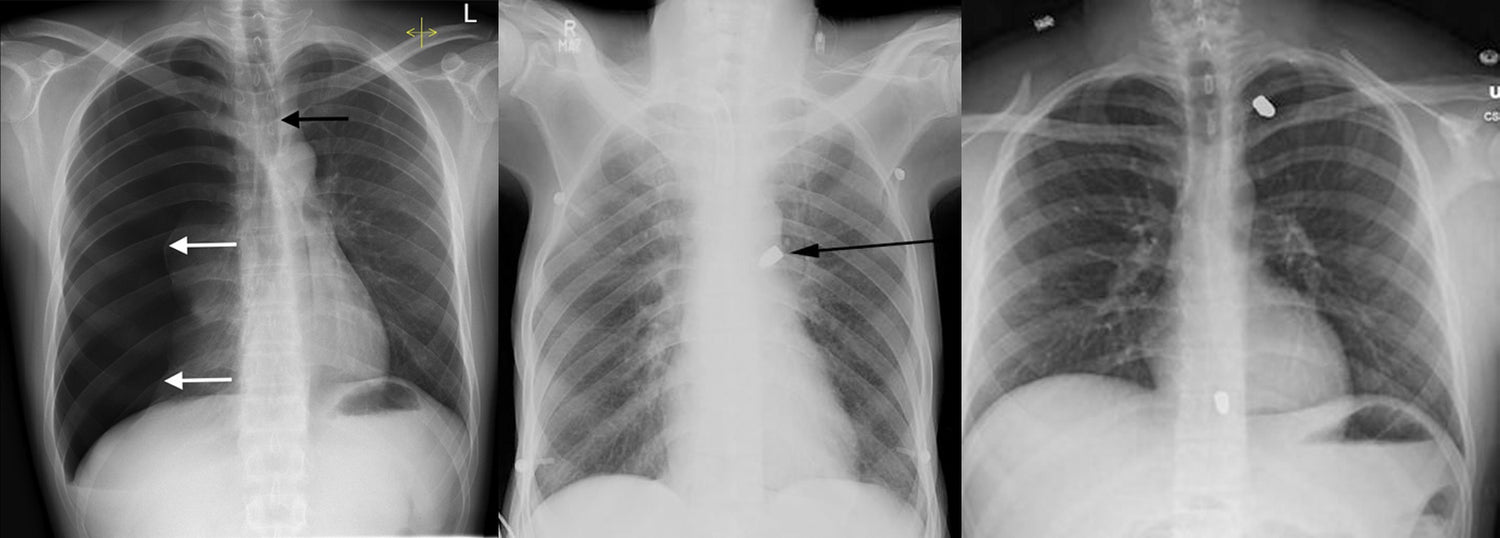

ThoraSite is an anatomical landmark guide, designed to provide a safer approach to the pleural space by pinpointing the procedure site. The device aids in identifying the appropriate intercostal space for lateral thoracostomies and similar procedures. ThoraSite is non-sterile and intended to be single-use.